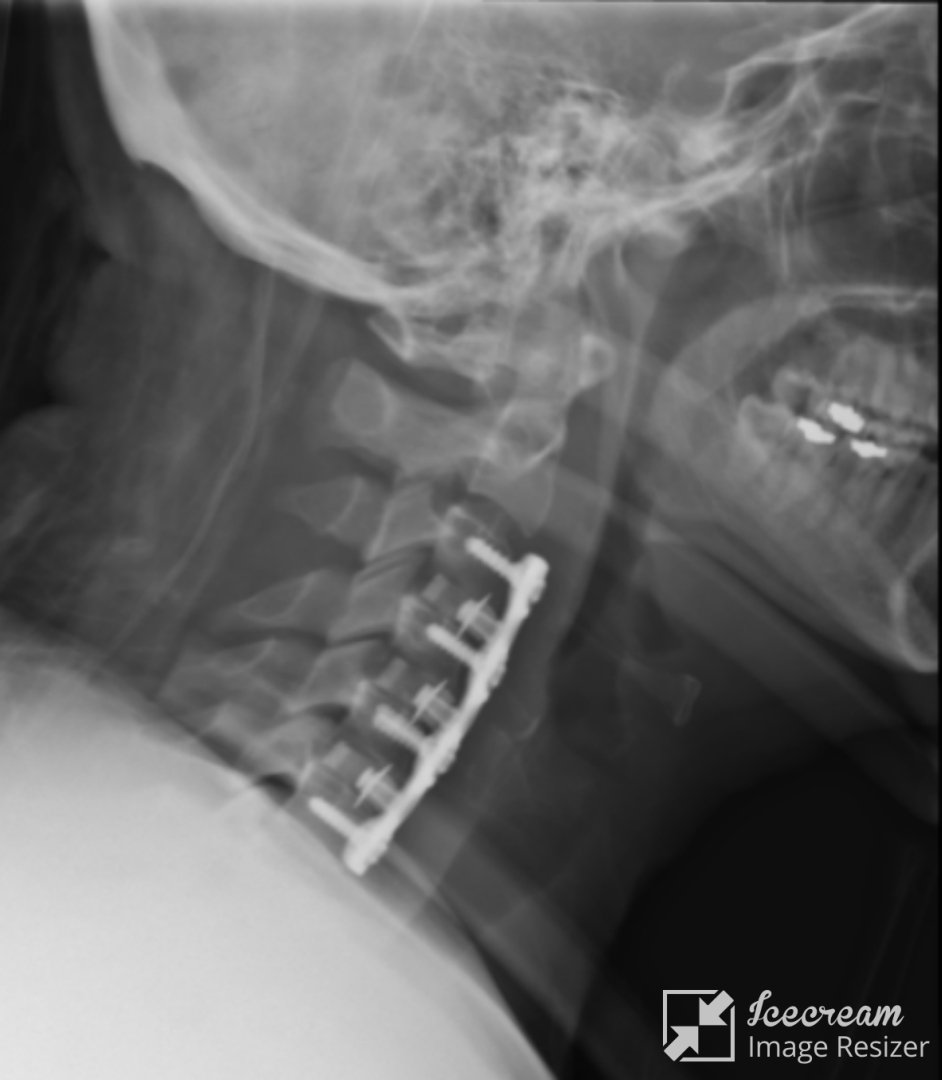

درمان جراحی و غیرجراحی دیسک کمر و گردن و تنگی کانال نخاعی

تشخیص و درمان  انواع شکستگی و دررفتگی و جابجایی ستون فقرات